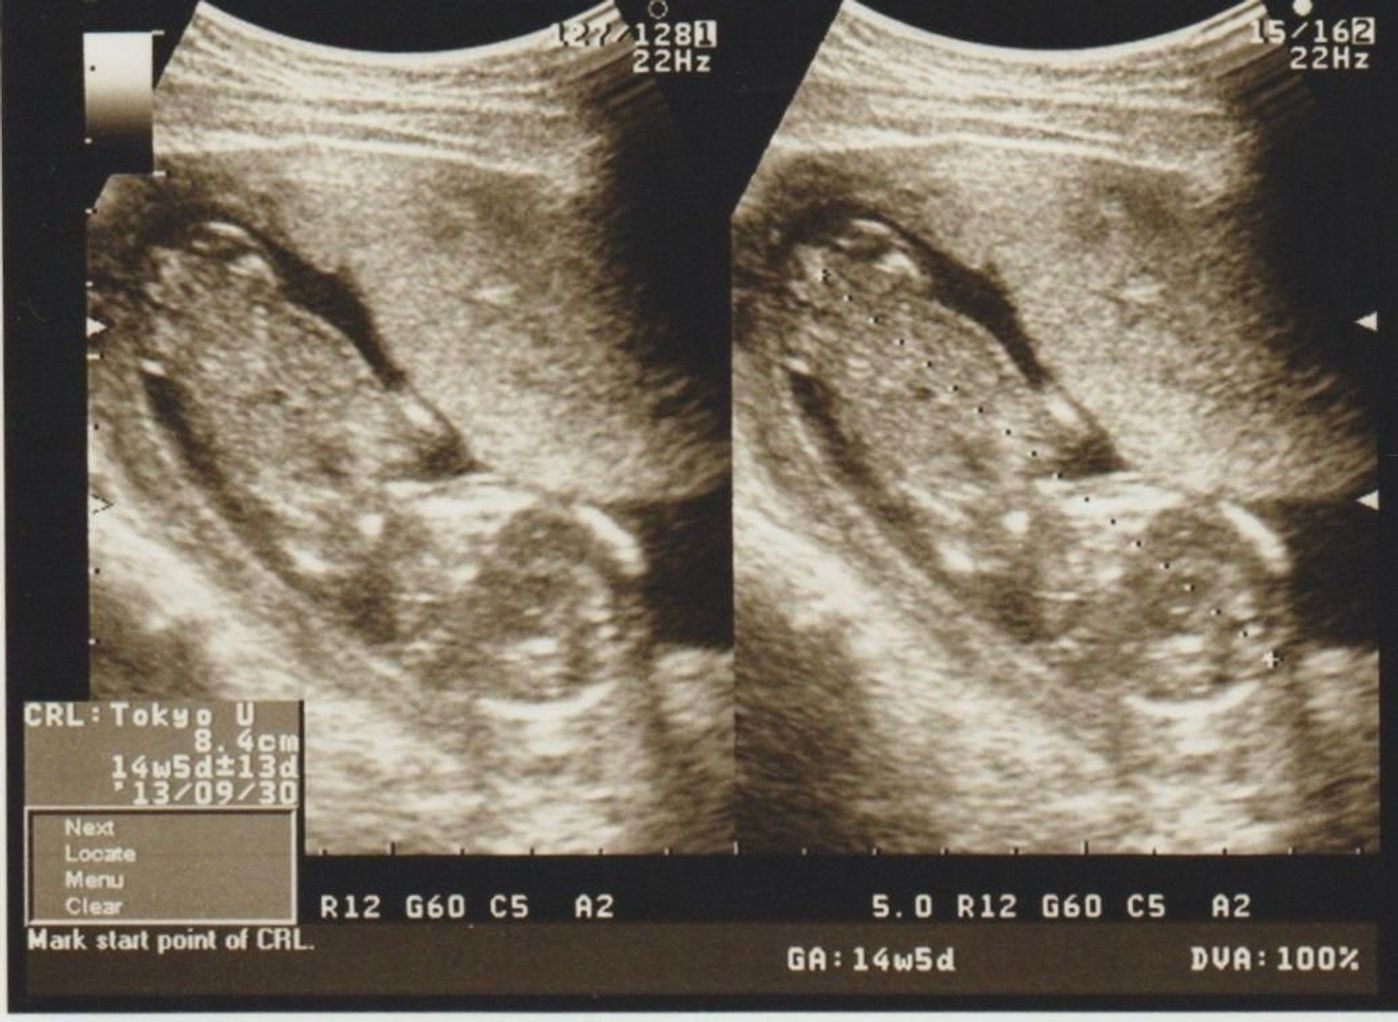

若い女性のエコー検査の様子を隠し撮りした映像です。 美容整形を受ける女性へ施術個所を事前に説明している映像です。 若い女性のエコー検査の様子を隠し撮りした映像です。 Total Videos 5 Total Size 818 Mb Resolution 19×1080 Download (ダウンロード) 3Dエコー写真のおすすめ時期は 早くても妊娠14週から、遅くても32週ごろ と言われています。 赤ちゃんの成長によって見え方が変わってきます。 全身を見たいか、顔の表情だけで十分なのか、病院と相談しつつ時期を決めるのがいいですね。 我が家は12 関税負担なし☆ECCO エコー STHREE レディース ゴルフシューズ ¥30,800 ¥23,500 23%OFF 13 関税負担なし☆ECCO GOLF BIOM G3 ゴルフシューズ ¥36,300 ¥24,500 32%OFF 14 関税負担なし☆ECCO エコー M Golf SThree GTX ゴルフシューズ

エコーでは全身が入っていますが、 子宮壁?やへその緒などに隠れて、 顔は全く見えませんでした。 手足がちょこんとついて、 お座りしているような様子は可愛いですが、 顔立ちが分からないので、少し物足りないですね。 23週0日 こちらは23週の時の キュアエコー 今回は、プリキュアオールスターズNewStageに登場する、キュアエコーの図案を紹介したいと思います。 まずは作った作品がこちら。 『キュアエコー』をアイロンビーズで作ってみた キュアエコー可愛いですね。 Theマジカル戦士!という感じの外見をしていると思います。 色・サイズ:OMBRE / 43 (265~27cm) サイズ感:期待していた通り このシリーズの紐タイプのサイズ42を使用していました。 サイズ感がピッタリ過ぎて、ワンサイズ上の43を今回頼んでみました。 やや余裕があり、期待通りのものでした。 色違いでeccoを